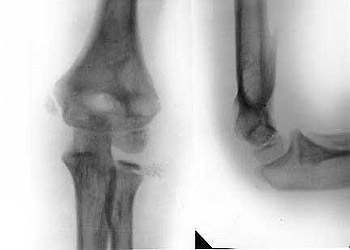

Fracture of humeral bone.